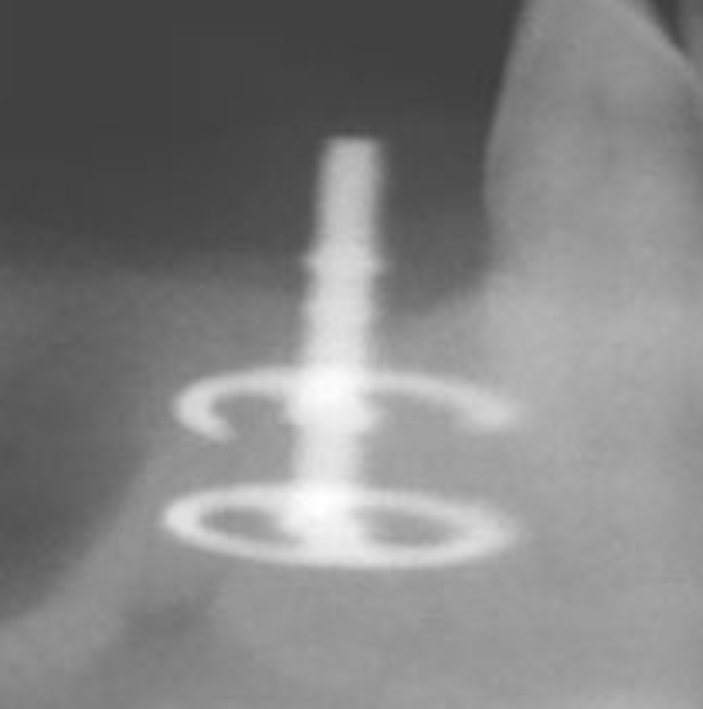

Diskimplantate

Diskimplantate sind scheibenförmige Implantate, die in der Horizontalen ausgedehnt sind. Sie hatten nach Angaben aus der Fachliteratur zumindest in der Vergangenheit wie die Blattimplantate dieselben Nachteile, eine hohe Bruchgefahr und eine schlechte Entfernbarkeit, die bei Entzündungen leider oftmals mit großen Knochenverlusten einherging.

Der Vorteil der Diskimplantate besteht nach Angaben des Herstellers in der Sofortbelastung durch die breitbasige Auflage, sowie der Einsatzmöglichkeit bei nur geringer Knochenhöhe.

Die leicht schräge Röntgenaufnahme (rechts) zeigt den Aufbau eines Diskimplantates.